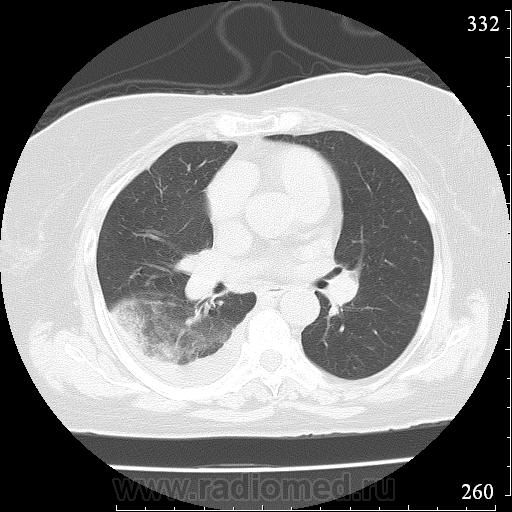

Еще один случай диагностики ТЭЛА методом КТ-ангиографии у женщины 59 лет. Основная клиническая жалоба - выраженная одышка. Определяется: полный дефект наполнения в системе правой ЛА (бифукация и нижнедолевая), неполный дефект наполнения в левой ЛА (нижнедолевая), пристеночные тромбы по задней стенке в области бифуркации обеих легочных артерий. Инфаркт (массивное кровоизлияние) нижней доли правого легкого. Правосторонний малый (120см3) гидроторакс. Несмотря на выраженные тромбы, поперечники легочных артерий - в пределах нормы.; на нативной (безконтрастной) КТ - тромбы не видны. Несмотря на почти полный дефект наполнения в левой нижнедолевой артерии, изменений в легочной ткани левого легкого нет. Также приводится топограмма, как вариант, приближенный к рутинной рентгенограмме